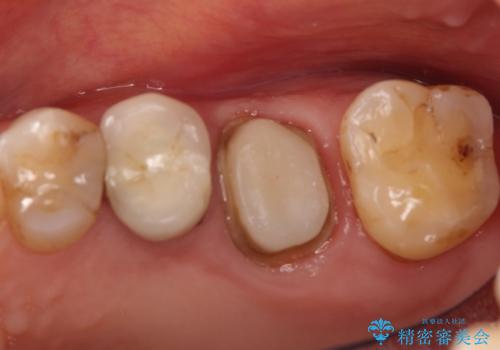

- 以前から奥歯に違和感があることを主訴に来院されました。歯肉にサイナストラクトを認めたため、再根管治療を行った後オールセラミッククラウンにて修復治療を行いました。根管治療は林先生に依頼しております。

根管治療の難易度に応じて根管治療認定医の先生を紹介させていただきます。

根管治療後は、破折リスクが高まるため被せものによる治療を提案いたします。